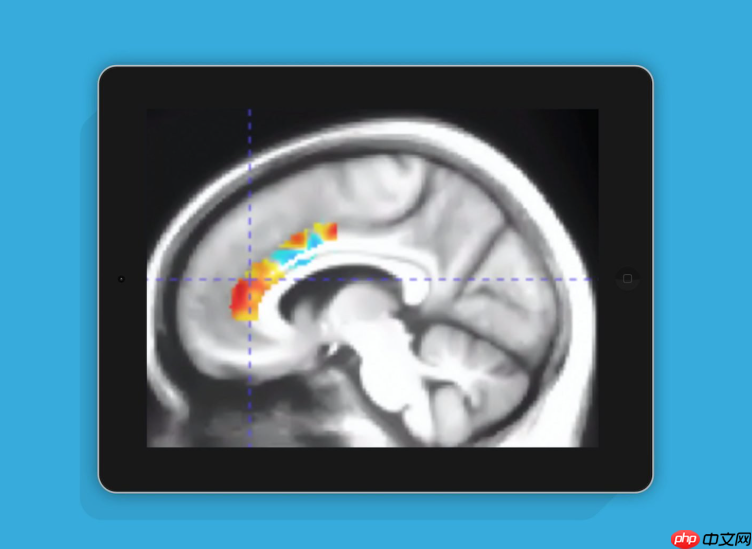

这项研究由美国Posit Science Corporation公司的Mouna Attarha领衔团队完成,并发表了一篇题为《Effects of Computerized Cognitive Training on Vesicular Acetylcholine Transporter Levels using [18F]Fluoroethoxybenzovesamicol Positron Emission Tomography in Healthy Older Adults: Results from the Improving Neurological Health in Aging via Neuroplasticity-based Computerized Exercise (INHANCE) Randomized Clinical Trial([18F]》的论文。该研究系统探讨了计算机化认知训练游戏对大脑退化相关神经指标的影响。

研究共招募了92名年长参与者,平均年龄为71.9岁,平均接受教育年限达16.5年。经过持续数月的实验干预,结果显示:连续进行10周特定大脑训练游戏的老年人,在认知功能方面表现出显著提升,其大脑功能状态相当于年轻了十年。